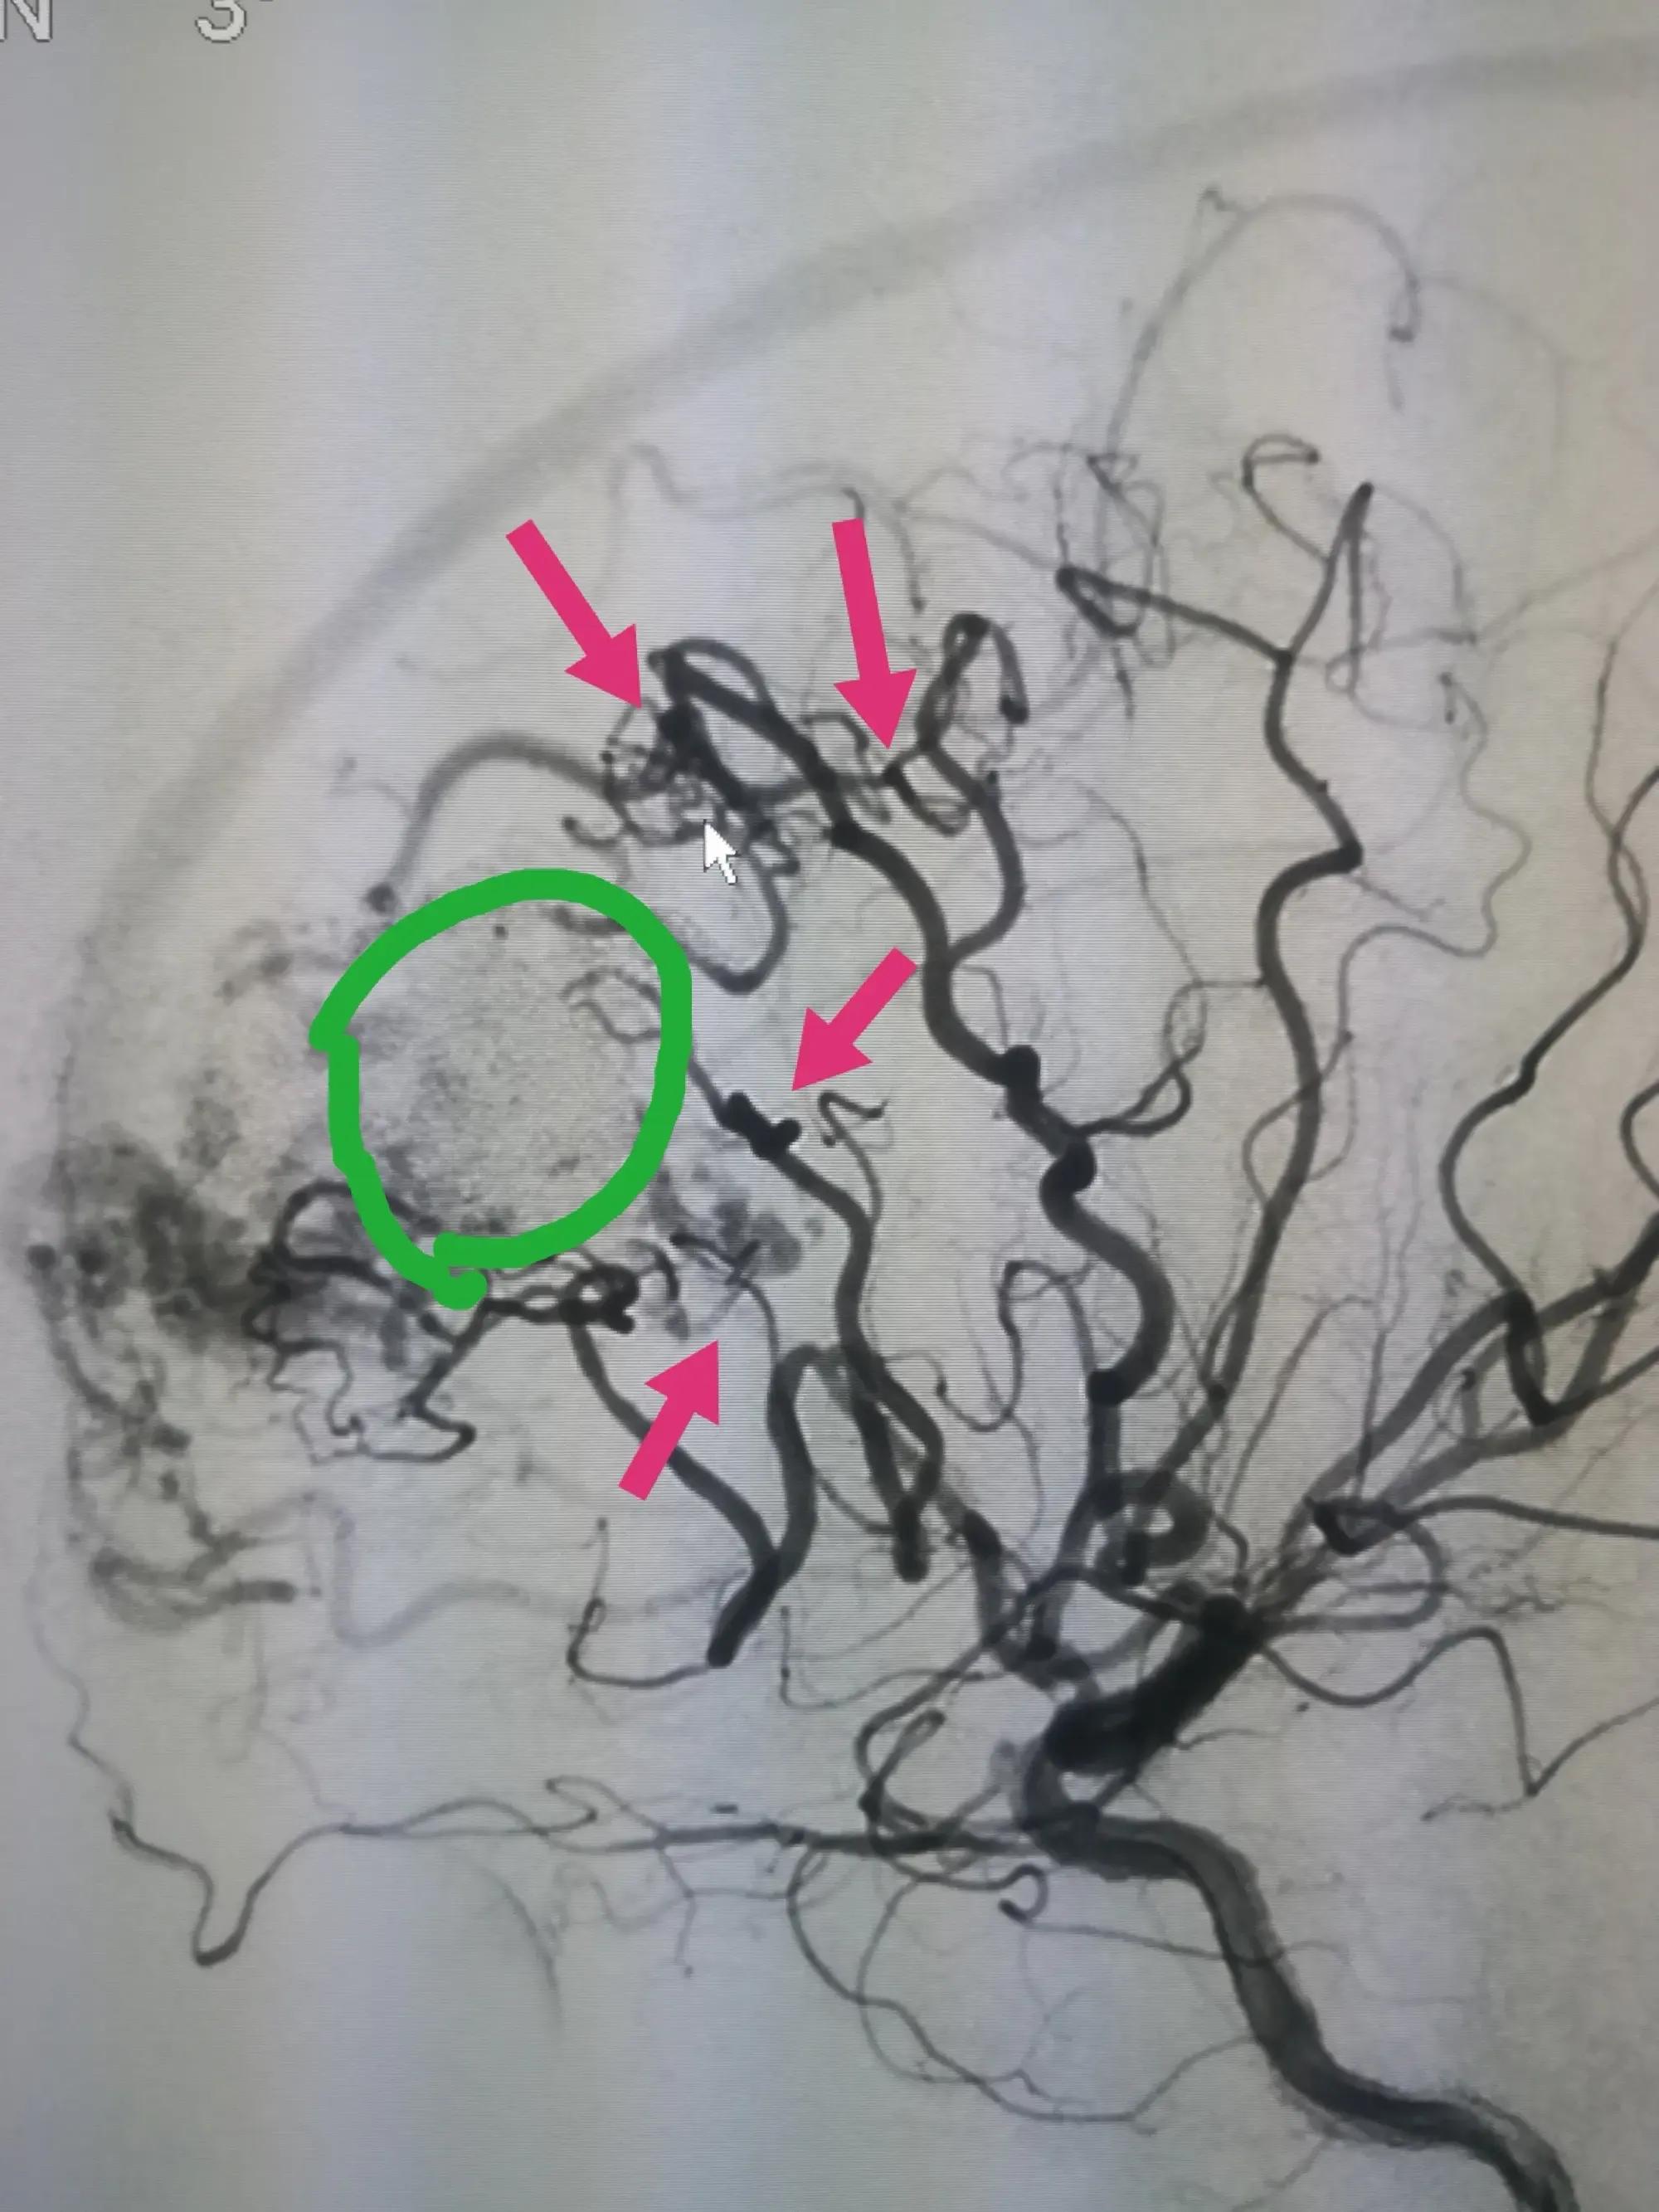

(4).数字减影血管造影:DSA是诊断颅内动脉瘤必须的“金标准”。

DSA提示脑动脉瘤